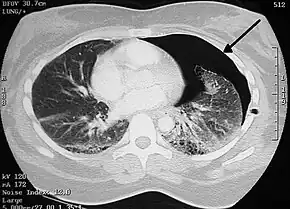

| A large right-sided spontaneous pneumothorax (left in the image). An arrow indicates the edge of the collapsed lung | |

Computed tomography

A CT scan is not necessary for the diagnosis of pneumothorax, but it can be useful in particular situations. In some lung diseases, especially emphysema, it is possible for abnormal lung areas such as bullae (large air-filled sacs) to have the same appearance as a pneumothorax on chest X-ray, and it may not be safe to apply any treatment before the distinction is made and before the exact location and size of the pneumothorax is determined.[14] In trauma, where it may not be possible to perform an upright film, chest radiography may miss up to a third of pneumothoraces, while CT remains very sensitive.[17]

A further use of CT is in the identification of underlying lung lesions. In presumed primary pneumothorax, it may help to identify blebs or cystic lesions (in anticipation of treatment, see below), and in secondary pneumothorax it can help to identify most of the causes listed above.[14][18]